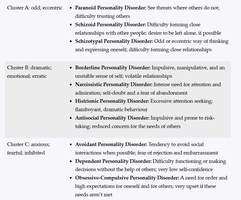

Personality disorders are enduring patterns of behavior, cognition, and inner experience that deviate markedly from cultural expectations, are inflexible, and lead to distress or impairment. The DSM groups these disorders into three clusters:

Cluster A: Odd, Eccentric Disorders

Paranoid Personality Disorder: Persistent distrust and suspicion of others, often interpreting their motives as malevolent.

Schizoid Personality Disorder: Detachment from social relationships and limited emotional expression.

Schizotypal Personality Disorder: Acute discomfort in close relationships, cognitive or perceptual distortions, and eccentric behavior.

Cluster B: Dramatic, Emotional, or Erratic Disorders

Borderline Personality Disorder (BPD): Instability in relationships, self-image, and emotions; impulsivity; intense fear of abandonment.

Narcissistic Personality Disorder (NPD): Grandiosity, need for admiration, and lack of empathy.

Histrionic Personality Disorder: Excessive emotionality and attention-seeking behavior.

Antisocial Personality Disorder (APD): Disregard for and violation of the rights of others, lack of empathy, and often criminal behavior.

Cluster C: Anxious or Fearful Disorders

Avoidant Personality Disorder: Social inhibition, feelings of inadequacy, and hypersensitivity to negative evaluation.

Dependent Personality Disorder: Excessive need to be taken care of, leading to submissive and clinging behavior.

Obsessive-Compulsive Personality Disorder (OCPD): Preoccupation with orderliness, perfectionism, and control, distinct from obsessive-compulsive disorder (OCD).